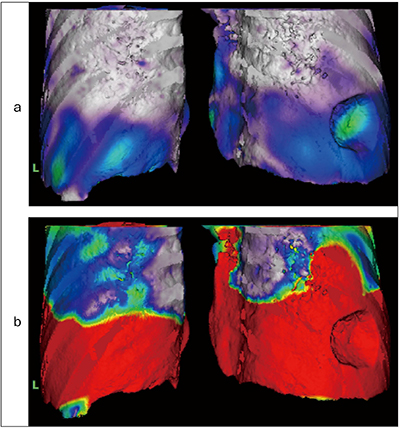

悪性であれば肺への浸潤や血管との関係も重要である。CTで動態撮影をしたデータにPhyZiodynamicsを用いることでフェーズ数増加、ノイズ軽減につながる。4Dシネの情報から、腫瘍は呼吸性に移動しており臓側胸膜由来の腫瘍が疑われる(図5a、b)。図5cの画像より、腫瘍は血管とは同期しておらず栄養血管はないと考えられる。また、癒着が強いとひきつられるので有茎性の腫瘍であると予測ができる。4Dモーション解析では、カラーマップは腫瘍部位、肺底と同様の分布をしており(図6)、さらにDynamic VOIで解析したグラフを見ても肺と同じ動きを示していることがわかる(図7)。

図5 PhyZiodynamicsによる画像作成(呼吸器外科領域)

a:シネ矢状断像 b:シネ冠状断像

c:胸壁と血管と腫瘍の位置関係のVR

図6 モーション解析によるカラーマップ(最大吸気のフェーズ)

a:velocity b:displacement